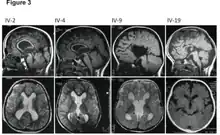

MRI images showing megalencephaly in four family members who all have unusually large skulls (the family is affected by an autosomal recessive syndrome caused by a KIF7 mutation that induces multiple epiphyseal dysplasia)[1]